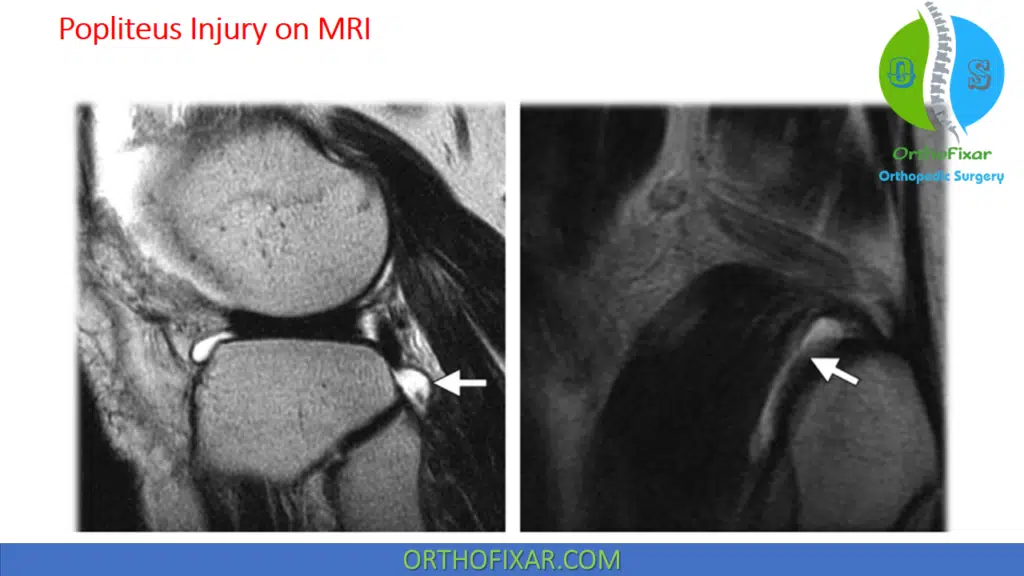

Imaging

MRI can be used to rule out rupture of the popliteus tendon. Thickening of the tendon may be identified on MR images.